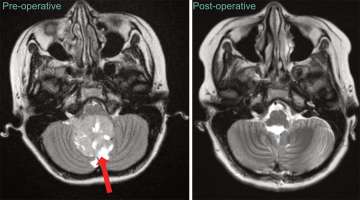

Being one of the world’s top research institutions, patients have access to world-renowned experts and state-of-the-art clinical research trials. We are committed to serving all children with pediatric brain and spinal cord tumors, even if treatment has been initiated elsewhere. Surgery is usually the first, and often most critical step in treating children with brain and spinal cord tumors. In addition to our exceptional experience in complex brain tumor surgery, we offer expertise in minimally invasive techniques, including endoscopy, laser interstitial therapy, and keyhole approaches. which allows us to safely and effectively treat tumors in difficult-to-access areas. When employed judiciously, these minimally invasive techniques serve to greatly reduce post-operative recovery time.

At UCLA, we use the most advanced technology to bring us closer to achieving our goal of surgical perfection. We have teamed with the virtual gaming industry to develop the latest technology in image-guided surgery. In an effort to enhance the safety of the surgeries we perform, we have adapted virtual reality technology for the operating room, allowing us to rehearse and prepare for surgery in a way that has never been possible before.